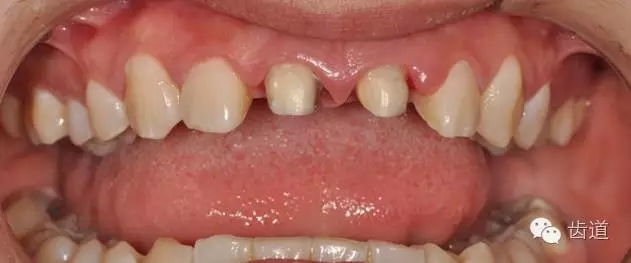

圖為拆除后的金屬冠修復(fù)體

基牙行完善的根管治療,臨時(shí)冠修復(fù),觀察,牙齦恢復(fù)。3個(gè)月后患牙無(wú)叩痛,無(wú)松動(dòng)。牙齦恢復(fù)良好。

11、21行根管預(yù)備,置2#PD纖維樁,樹(shù)脂恢復(fù)部分牙體,修整。